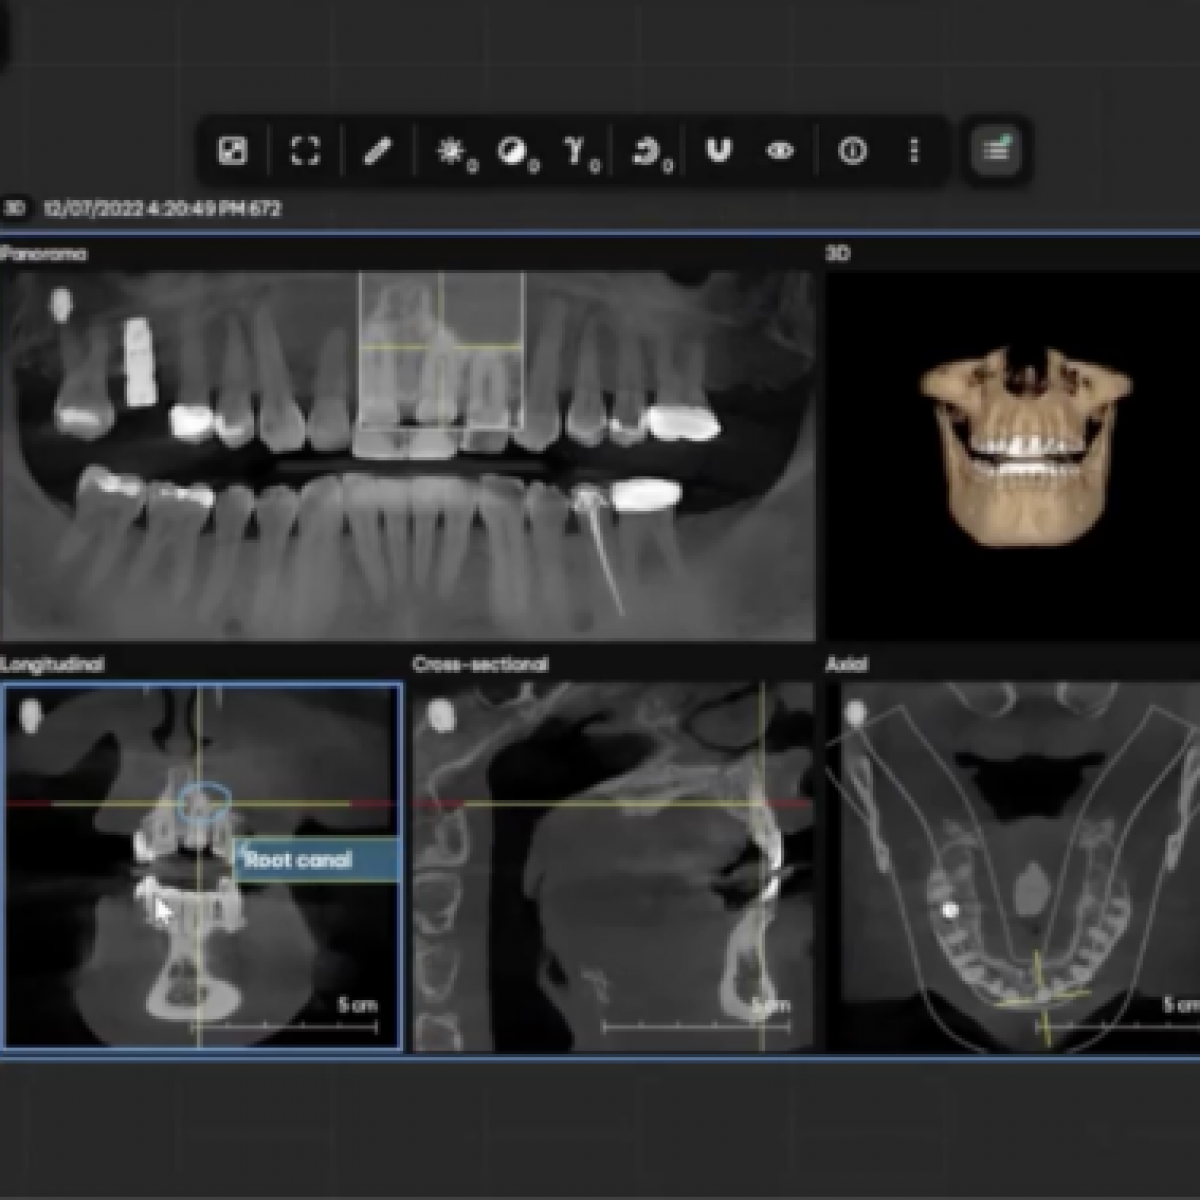

In line with the expanded options for uploading historical X-ray images to DS Core, the Communications Canvas in DS Core has also received several updates: Firstly, the Communication Canvas now remembers the individually set-up arrangement of media and existing annotations from a previous session for a patient, to allow the dentist to dive right into the prepared patient conversation. This makes it easier to prepare for the patient consultation and supports the evaluation of the case.

Secondly, the annotation tool has been extended. Freehand and text comments can now also be added to 3D X-ray images, not just 2D images. Relevant findings can be highlighted during consultation and used for effective patient communication.

Users can delete, edit, hide and track the annotations on slice views of the 3D X-ray image.